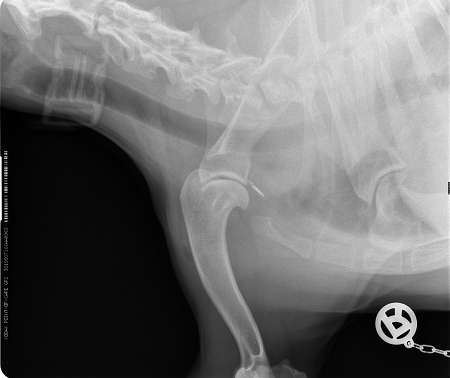

Das Ergebnis der Untersuchung war dann aber doch überraschend: Schulter, Ellenbogen und auch Lendenwirbelsäule sehen in Bezug auf Arthosen und Spondylosen erstaunlich gut aus. Allerdings hat das Mortadellchen in der Halswirbelsäule kaum noch Bandscheiben, so dass Stöße und Erschütterungen, wie sie schon nur im (heftigeren) Spiel oder bei ihren heiß geliebten Purzelbäumen und Judorollen auftreten, sehr schnell zu Schmerzen und im Extremfall auch zu Schlimmerem führen können.

Hier mal die relevante Röntgenaufnahme. Btw: Sooooo klein, wie mancher denkt, ist ein Microchip nicht….